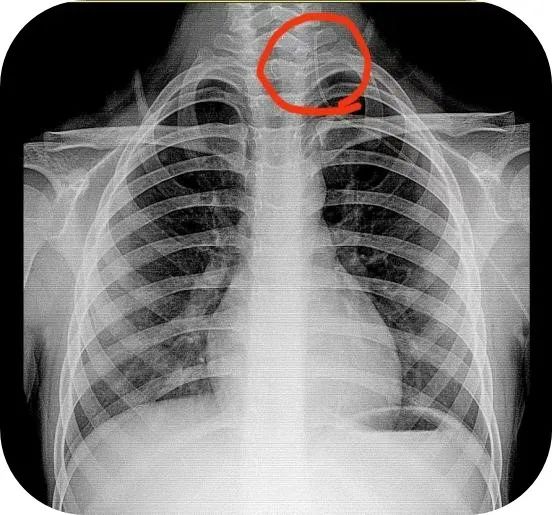

1 床王先生,入院拍摄 X 线胸片,显示 PICC 导管漂浮到颈静脉,于是特别紧张地追问小李护士……

2021 年 INS 指南中关于中心血管通路装置(CVAD)异位的概念可以分为原发性和继发性两种。其中,导管继发性异位是指 PICC 导管置入时末端位置准确,但在使用过程中导管末端位置发生移位,离开准确位置,这在导管留置的任何时间段都可能发生。异位主要发生于颈内静脉、腋静脉、锁骨下静脉等部位,其中颈内静脉异位发生率最高。这种情况我们一般可以通过 X 线胸片及时发现。